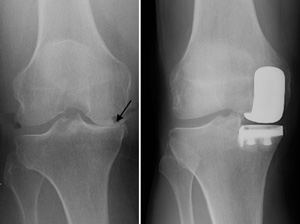

X-rays of a good candidate for partial knee replacement. (Left) Severe osteoarthritis limited to the medial compartment. (Right) The same knee after partial knee replacement.